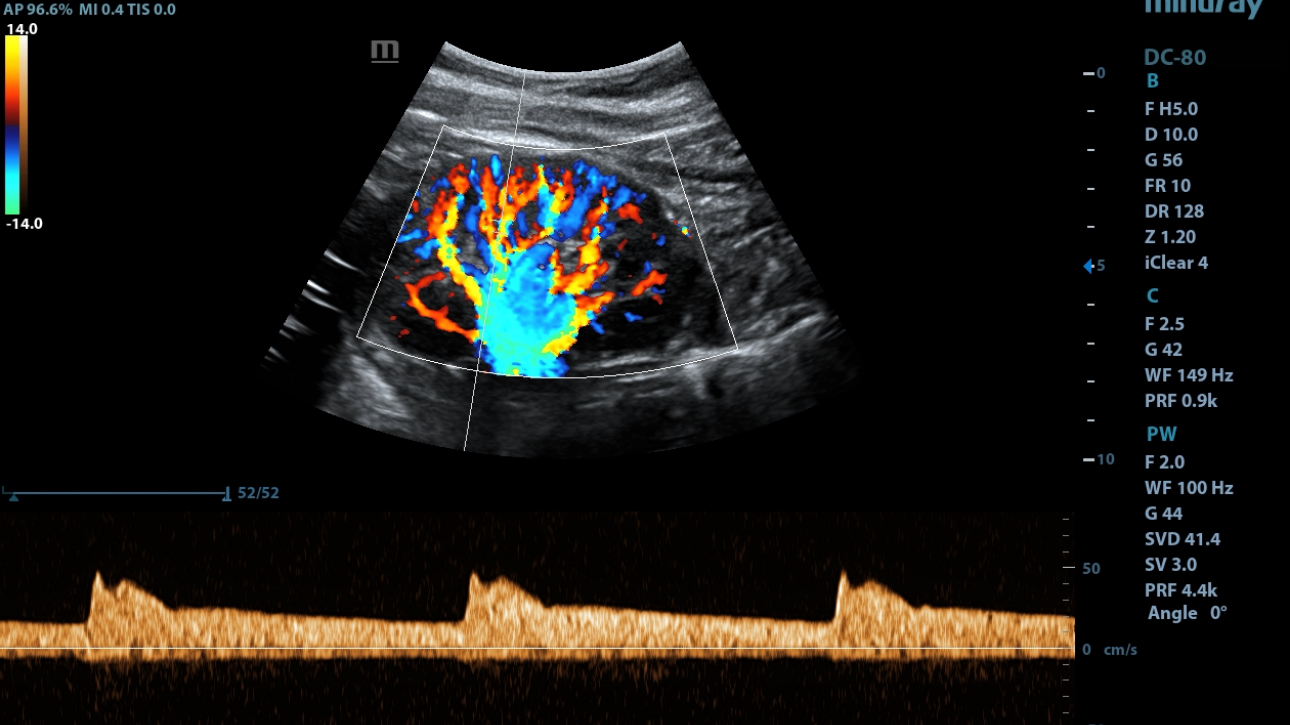

eXceptional Intelligence

Intelligence throughout entire workflow

Intelligence integrated in professional diagnostic tools for whole examination procedures,DC-80 with X-Insight provides exceptional intelligence integrated in professional diagnostic tools across wide applications and throughout whole examination procedures, from regular screening to further diagnosis and clinical follow up.

Smart Track

ItŌĆÖs Mindray unique feature to reduce repetitive, time-consuming scanning steps in vascular exams. Smart Track provides intelligent and real-time vessel tracking and real-time image optimization of Color and PW.